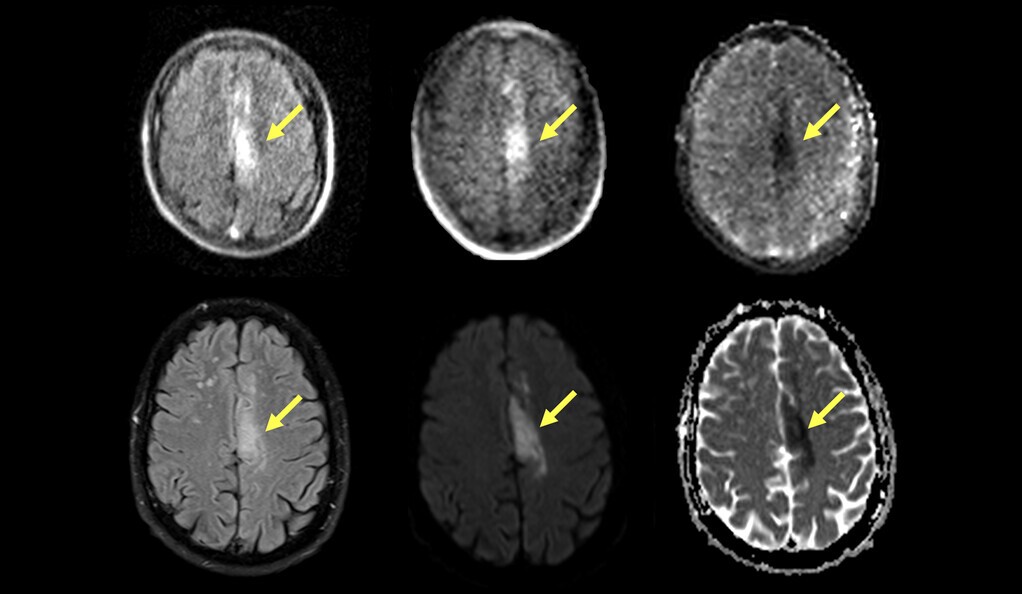

Cada paciente se sometió a resonancias magnéticas convencionales para confirmar un diagnóstico de accidente cerebrovascular isquémico. Luego fueron escaneados con la máquina de resonancia magnética portátil, que podía detectar con precisión coágulos de sangre en el cerebro en el 90 por ciento de la cohorte.

La máquina portátil se probó en una variedad de salas de emergencia y escenarios de cuidados intensivos. Se encontró que detecta coágulos de sangre tan pequeños como 4 mm de diámetro.